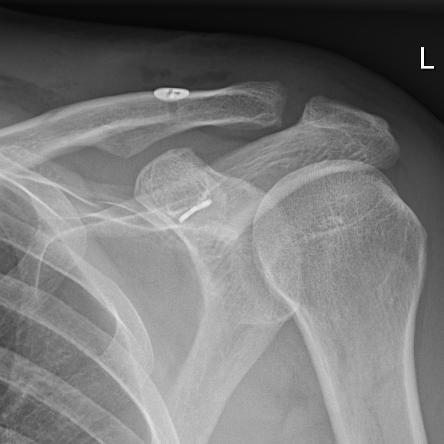

Einklemmungssymptome der Supraspinatussehne am Schultergelenk sind sehr häufig. Meist können diese jedoch konservativ mit gezielten Muskelkräftigungsübungen behandelt werden. Liegen jedoch schon Risse in der Sehne vor, so müssen diese oftmals wieder angenäht werden.

Therapie von Rissen der Rotatorenmanschette (Rotatorenmanschettenruptur)

Häufig finden sich ab dem 60. Lebensjahr Risse in der sog. Rotatorenmanschettenmuskulatur. Diese führen zu Schmerzen und Funktionseinschränkungen. Je nach Größe des Risses können diese meist arthroskopisch wieder angenäht werden. Selten werden mini-offene Operationen noch angewandt. Bei irreparablen Rupturen können auch einmal Sehnentransferoperationen oder Ersatzplastiken (beim jungen Patienten) vorgenommen werden. In Einzelfällen kann die Sehne auch verstärkt werden (autologe Sehne, Patches). Diese sind allerdings gegenüber künstlichen Gelenken beim älteren Menschen abzuwägen.